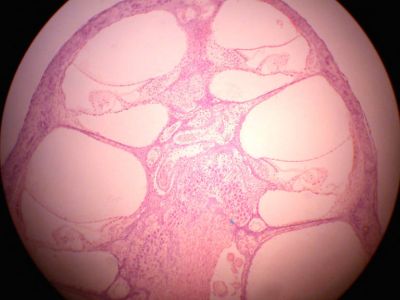

Inner ear - histology slide

This is a histology slide of the inner ear.

Histology slide courtesy of Florida State University.